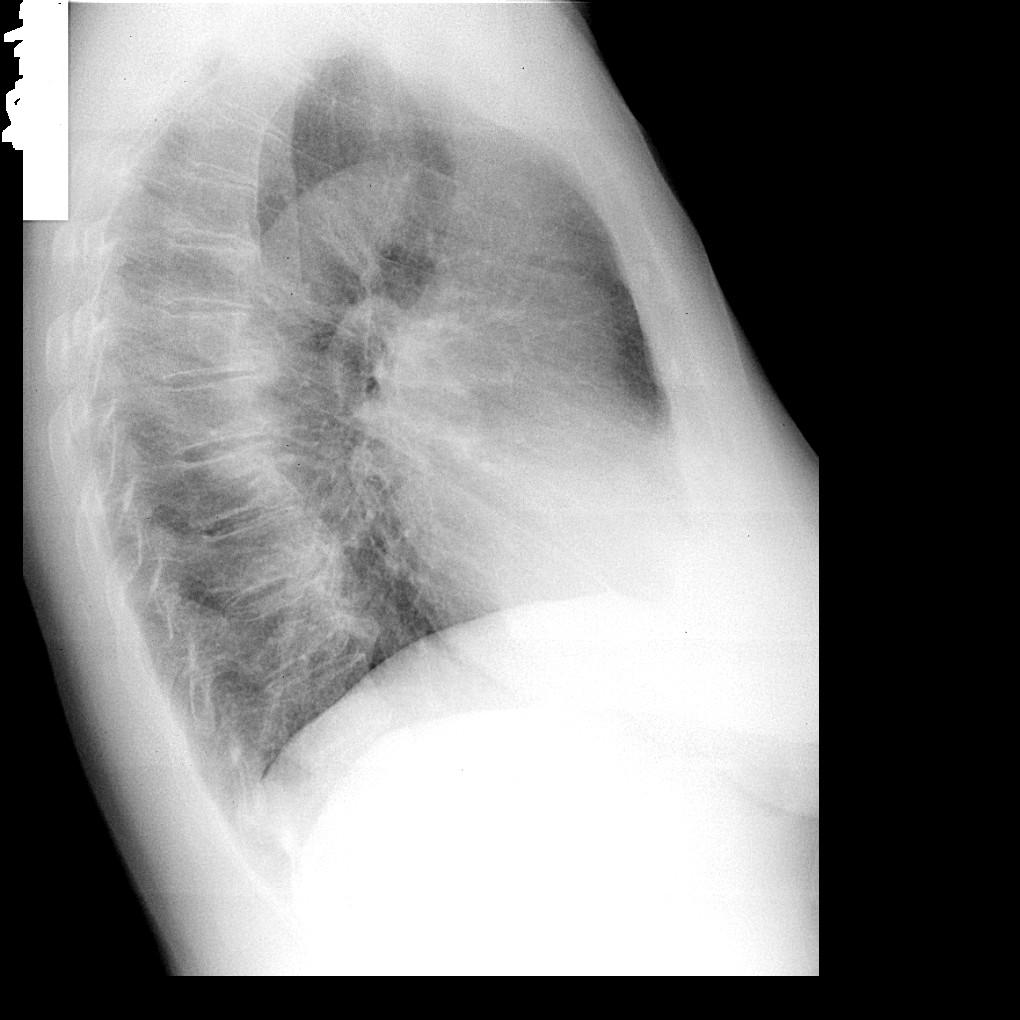

Локальное усиление пневмофиброза здесь симптом совершенно малозначительный. Что-то есть в S9 и в S4. Существеннее тут расширение и ухудшение структурности корней, особенно правого.

Думаю, что игра ЛР и ребер. А корни не смущают?